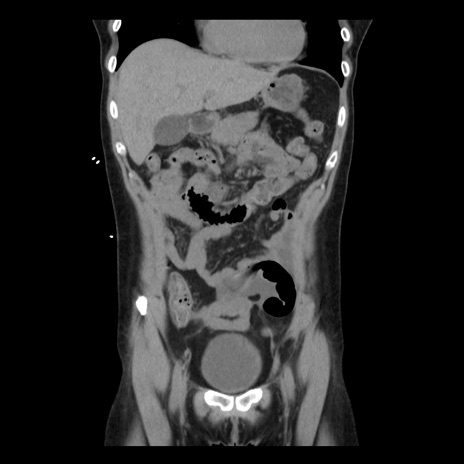

症例10(冠状断像)

【症例】 50歳代女性

【主訴】 腹痛

【現病歴】前日生レバーを食べた。今朝に排便あり。 昼前に突然発症の腹痛を生じ、当院救急外来を受診した。

【既往歴】 子宮筋腫にてで子宮全摘後

【身体所見】 意識清明、腹部:平坦、軟、下腹部やや左を中心に圧痛・反跳痛あり、筋性防御あり

【データ】WBC 7800、CRP 0.07